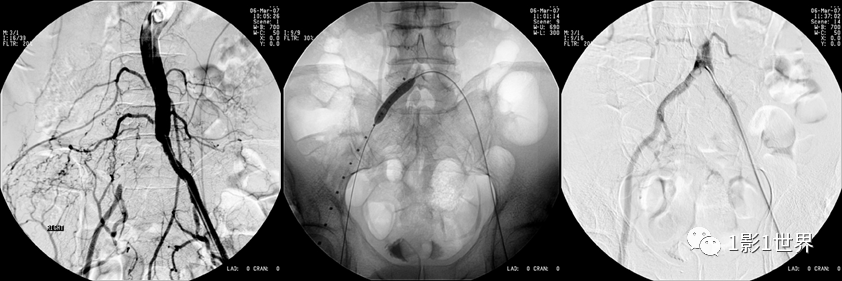

糖尿病20年,左下肢疼痛、间歇性跛行5年,静息痛1年,加重并变黑2个月。住院后下肢CTA示左下肢血管广泛不光滑,节段性轻度狭窄,其中最严重的是左侧股浅动脉中段重度狭窄(约90%),长度约8cm。

介入科DSA血管造影,确认了CTA诊断,同时行球囊扩张,支架置入术,再次造影,股动脉再通,远端血流较好。

什么是外周支架话说介入 | 外周血管狭窄,支架植入术_https://www.jmylbn.com_新闻资讯_第8张术后病人症状缓解,半年后复查血管通畅。